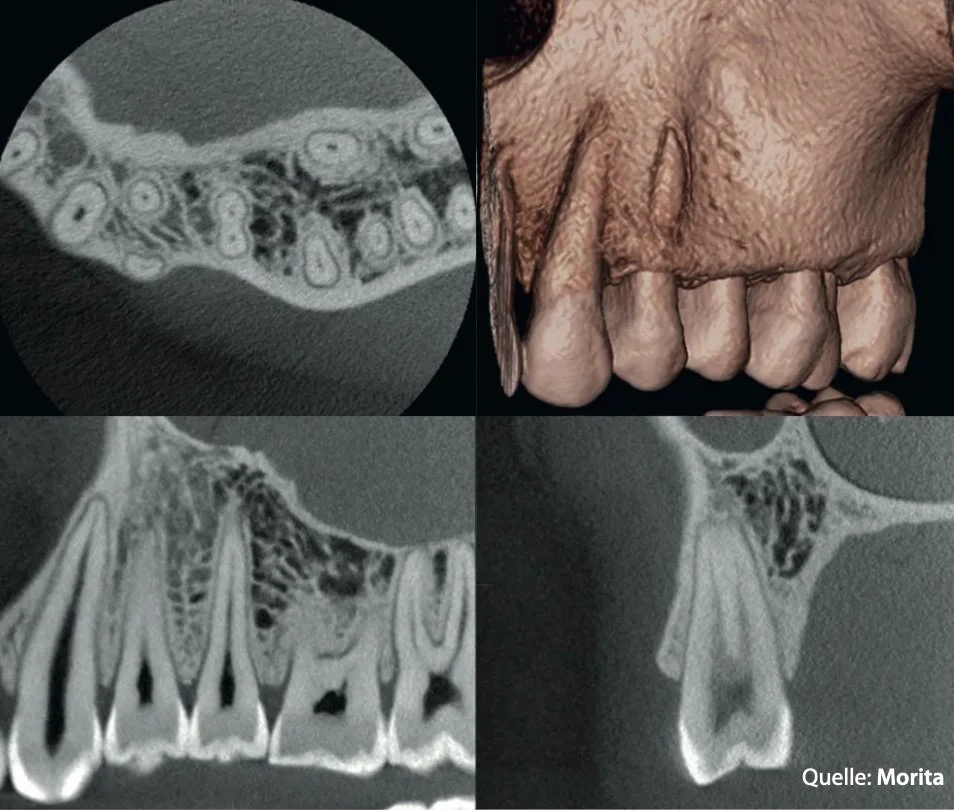

DVT: Röntgenbilder in der 3. Dimension

Ein DVT – Digitaler Volumentomograph – ist ein hochmodernes Röntgengerät, das eindreidimensionales Bild von Zähnen, Kiefer und den umliegenden Strukturen erstellt.

Während herkömmliche zweidimensionale Röntgenaufnah-men nur flache Schatten zeigen, macht das DVT die Situation räumlich sichtbar – bis ins feinste Detail. So lassen sich zusätzliche Wurzelkanäle, Knochendefekte, anatomische Varianten oder verborgene Entzündungen erkennen, die sonst unsichtbar bleiben.

So können wir Ihren Zahn vorab virtuell planen, um bei Ihrem Besuch perfekt vorbereitet zu sein.